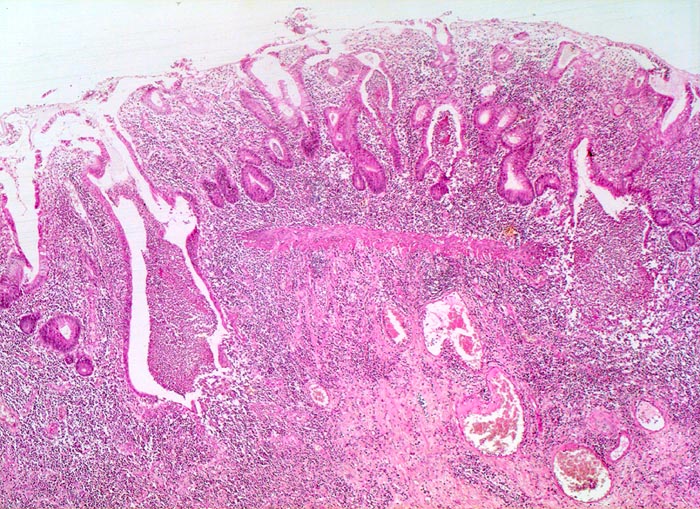

PathoPic – image database / PathoPic ID 5076 - Colitis ulcerosa

Colitis ulcerosa

Schwer gestörte Kryptenarchitektur mit zahlreichen verzweigten und unregelmässig geformten Krypten. Das Entzündungsinfiltrat in der Lamina propria ist stark verdichtet und greift auf die fibrosierte Submukosa über. Mehrere Kryptenabszesse. Die Krypten enden deutlich oberhalb der Lamina muscularis mucosae (Zeichen der Atrophie).

Kolektomie wegen chronischer therapierefraktärer Kolitis.